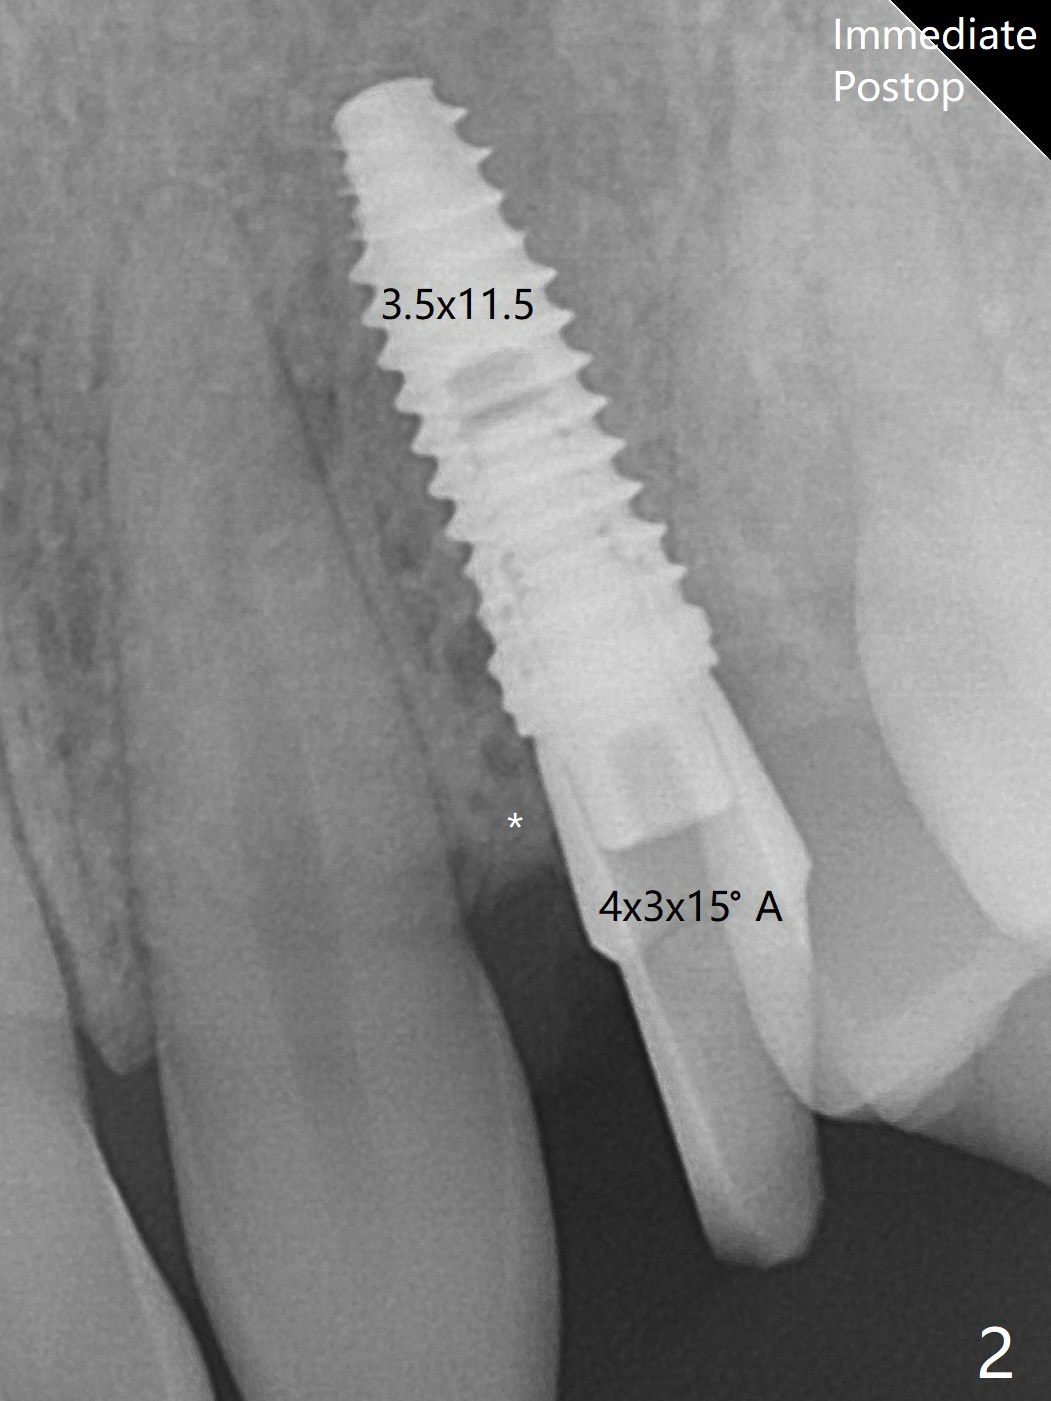

There is mesial crestal bone loss 4 months postop (Fig.4, as compared to immediate postop in Fig.2 (*)).